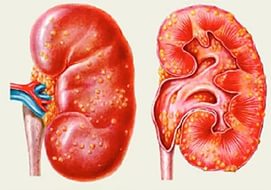

Гломерулонефрит — это серьезное заболевание, при котором поражается клубочковый аппарат почек. Обычно оно возникает в результате иммунного воспалительного ответа организма на инфекцию, чаще всего вызванную стрептококками.

Во время обострения у больных наблюдается повышение температуры тела и тупая ноющая боль в области поясницы. Клинический анализ мочи показывает нарушения в работе почечной мембраны, что проявляется в значительном количестве белка в моче.

Поскольку с мочой выводится большое количество белка, его уровень в крови снижается. Существует закономерность: при уменьшении содержания белковых элементов в крови начинают возникать отеки, которые особенно выражены по утрам. Этот симптом является характерным для гломерулонефрита.

У пациентов с хроническим гломерулонефритом практически всегда фиксируется повышение артериального давления. Это связано с тем, что в клубочках почек находятся структуры, которые вырабатывают вещества, регулирующие уровень артериального давления.